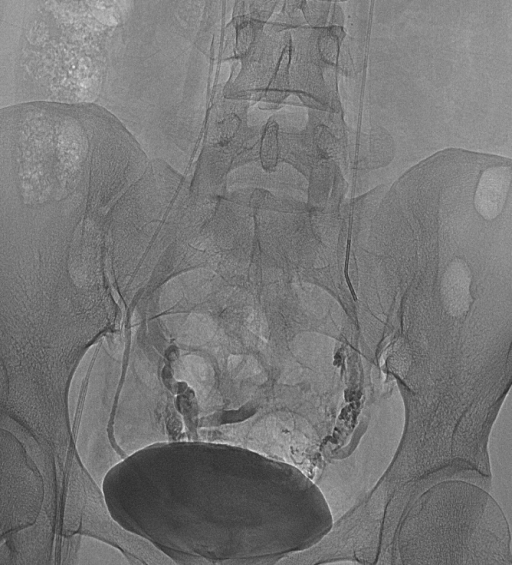

![]() 1.彩超检查 彩超检查可以发现卵巢静脉及静脉丛迂曲扩张,卵巢静脉血流缓慢或返流。 ![]() 2.增强CT及MRI检查 可显示子宫附件内迂曲、扩张的静脉血管结构。 ![]() ![]() ![]() 3.经皮导管逆行卵巢静脉造影术 目前认为是盆腔淤血综合征诊断金标准。 ![]() ![]() ![]() ![]()

介入治疗是目前公认的盆腔淤血综合征的首选治疗方案。 盆腔淤血综合征的介入治疗是在局部麻醉状态下,通过股静脉穿刺或颈静脉,引入导丝、导管,插入到盆腔静脉,进行盆腔静脉造影及予以硬化剂、金属弹簧圈等予以栓塞,将有病变扩张的盆腔静脉进行封闭,从而达到治疗的目的。 ![]() ![]() 盆腔淤血综合征的介入治疗具有安全性高、创伤小、效果确切、不影响月经及生育的特点。 在四院接受介入治疗后,困扰刘女士四年多的盆腔瘀血综合征终于得到解决,目前已经康复出院。 |